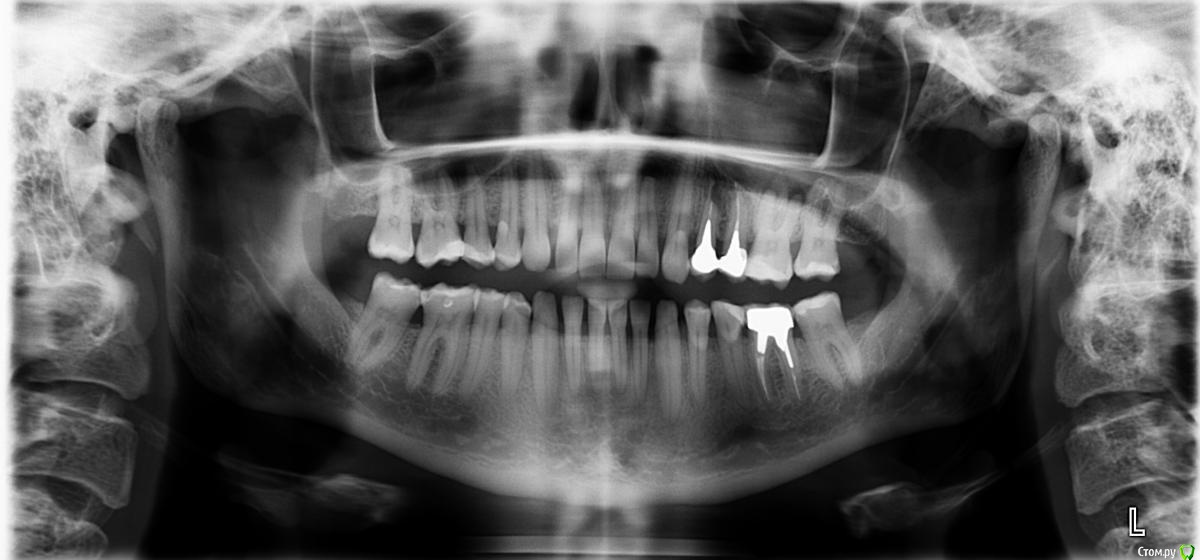

TAP Опубликовано 9 марта, 2016 Поделиться Опубликовано 9 марта, 2016 Добрый день! Уважаемые доктора, подскажите, 24 зуб возможно ли сохранить? Ссылка на комментарий

IvanK Опубликовано 9 марта, 2016 Поделиться Опубликовано 9 марта, 2016 я бы еще обратил внимание на: 26, 25,35 Ссылка на комментарий

TAP Опубликовано 9 марта, 2016 Автор Поделиться Опубликовано 9 марта, 2016 (изменено) Да была резекция26 сейчас после снимка положили лекарство, лечат гранулему Изменено 9 марта, 2016 пользователем TAP Ссылка на комментарий

red_butler Опубликовано 10 марта, 2016 Поделиться Опубликовано 10 марта, 2016 2.4 удаляйте Ссылка на комментарий

red_butler Опубликовано 10 марта, 2016 Поделиться Опубликовано 10 марта, 2016 Т е сохранить никаких шансов или просто так целесообразнее?Именно не целесообразно. Можно конечно провести повторную РВК, но если это сделать правильно, то в финансовом плане будет сопоставимо с имплантацией а прослужит зуб меньше импланта. Ссылка на комментарий

red_butler Опубликовано 11 марта, 2016 Поделиться Опубликовано 11 марта, 2016 Желание большое именно сохранить, здесь не в вопросах экономии речь. Просто из лечащих врачей никто ничего кроме удаления не предложил, поэтому если кто подскажет, как дальше быть или кто конкретно может помочь, буду очень признателен!Тогда потребуется повторная пере апикальная хирургия с ретроградным пломбированием корневых каналов. 1 Ссылка на комментарий

IvanK Опубликовано 12 марта, 2016 Поделиться Опубликовано 12 марта, 2016 Себе бы тоже попытался сохранить Тогда потребуется повторная пере апикальная хирургия с ретроградным пломбированием корневых каналов.+1 Ссылка на комментарий